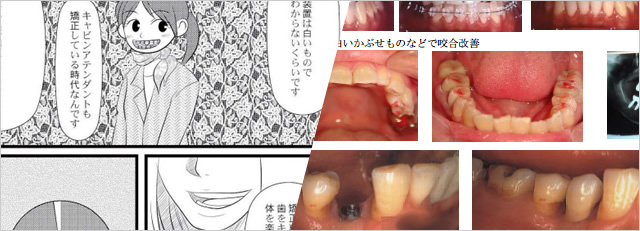

白い装置と白いワイヤーで見た目も目立たずクリアスナップで整体にやさしい力で痛みの減少・短期間(8ヶ月~1年半)治療ができます。

すでに填め物・冠せ物をしているのであれば、それらを除去して型取り(印象)して合着する方法(2回治療)填め物・冠せ物を入れた時の、咬み合わせ調整方法について、今の歯科界では患者様に「高いですか」「どうですか」と聞いて患者様からOKがでれば終了します。いわゆる患者様主体の、咬み合わせ調整方法です。

アカデミー歯科は患者様からOKが出てから首や腰の痛みがあればそれが消えるまで咬み合わせ調整する歯科医師主体の、咬み合わせ調整法です。まさしく「体をみて歯をみる医療が主体です。」

貼り爪のように白い歯をひっつける方法(ラミネートベニア)、今すぐに矯正治療のできない患者様にはもってこいの治療方法です。